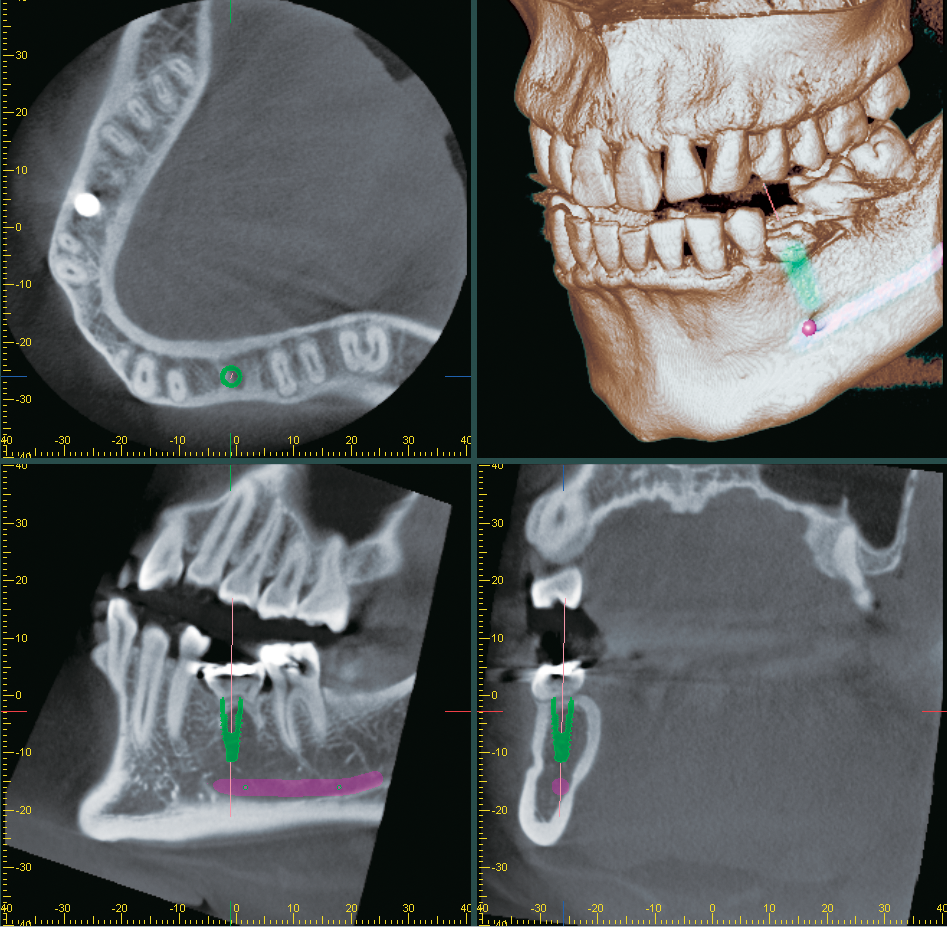

3D Diagnostix Digital Services Now Integrated with Morita i-Dixel Imaging Software

Morita’s i-dixel software_screen capture alternate text for this image

J. MORITA USA, world-leader in imaging technology, has made the following announcement regarding a new partnership with 3D Diagnostix Digital Services. In an effort to provide dentists with technological innovations that will enhance patient outcomes, US-guided surgery provider, 3D Diagnostix recently decided to join forces with the leading dental/medical manufacturer, Morita for a direct connection … Read more